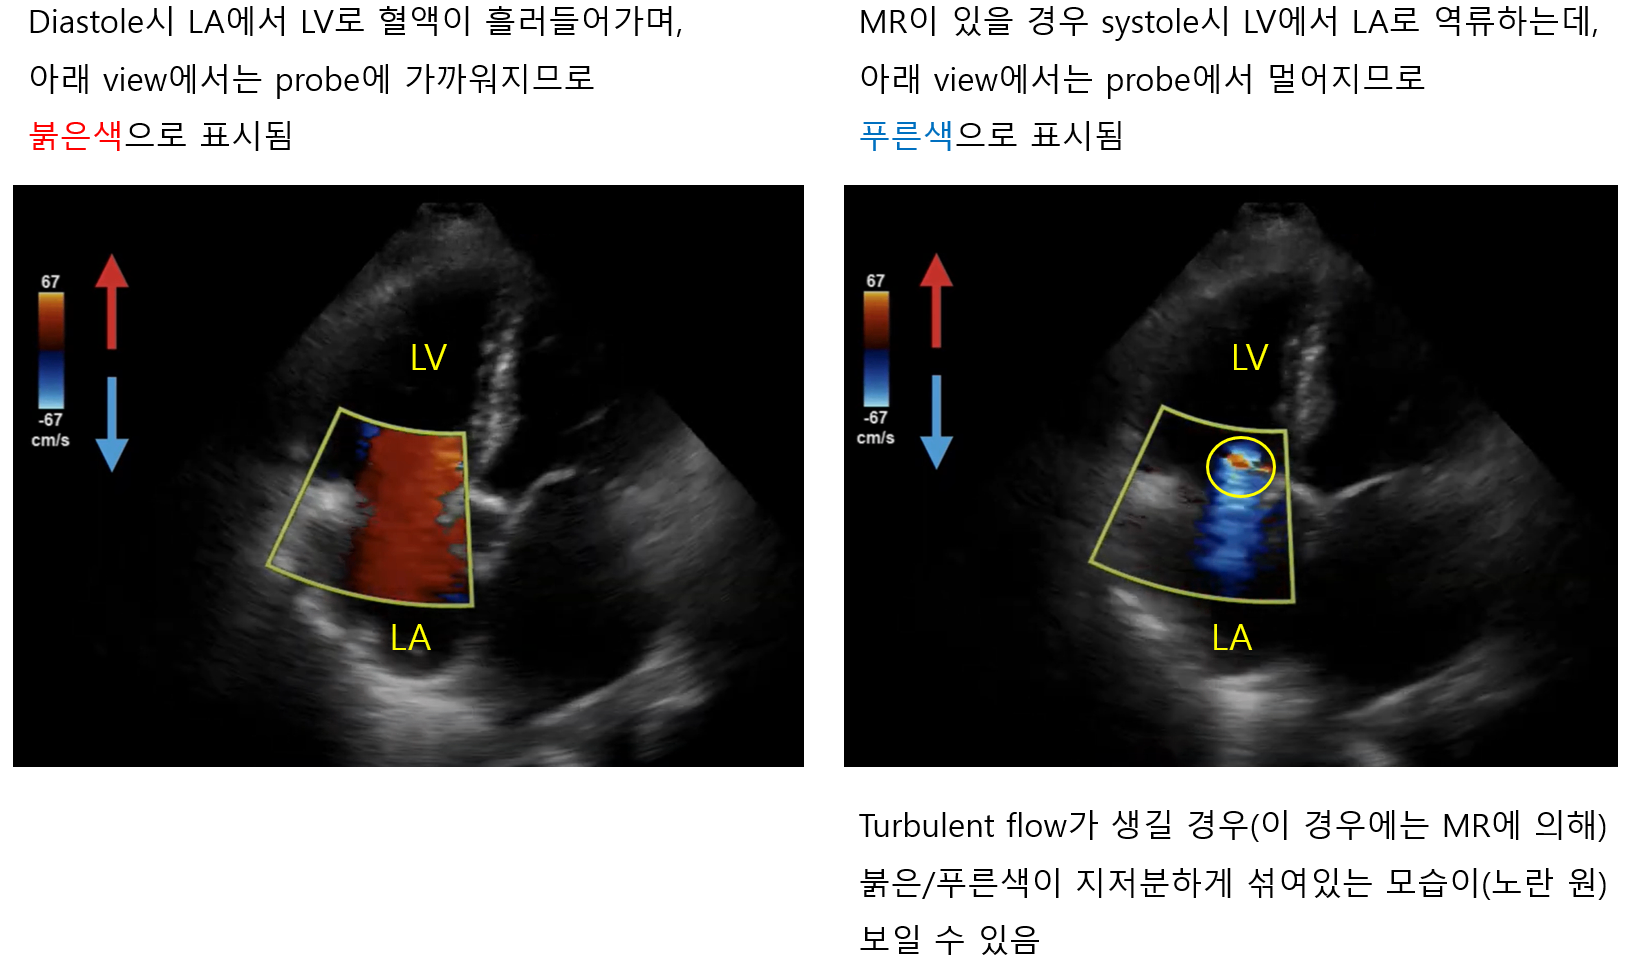

3) 도플러 심초음파(Doppler echocardiography)

(1) 도플러 효과: 초음파가 움직이는 물체(= 혈류)에 부딪혀 반사될 경우, 파장이 원래의 파장보다 달라지는 현상

(2) 도플러 효과를 통해 혈류가 초음파로부터 얼마나 빠르게 가까워지는지/멀어지는지를 측정할 수 있음

(3) Color Doppler, pulse wave Doppler, continuous wave Doppler 등이 있으며, 주로 국시에서는 color가 주어짐